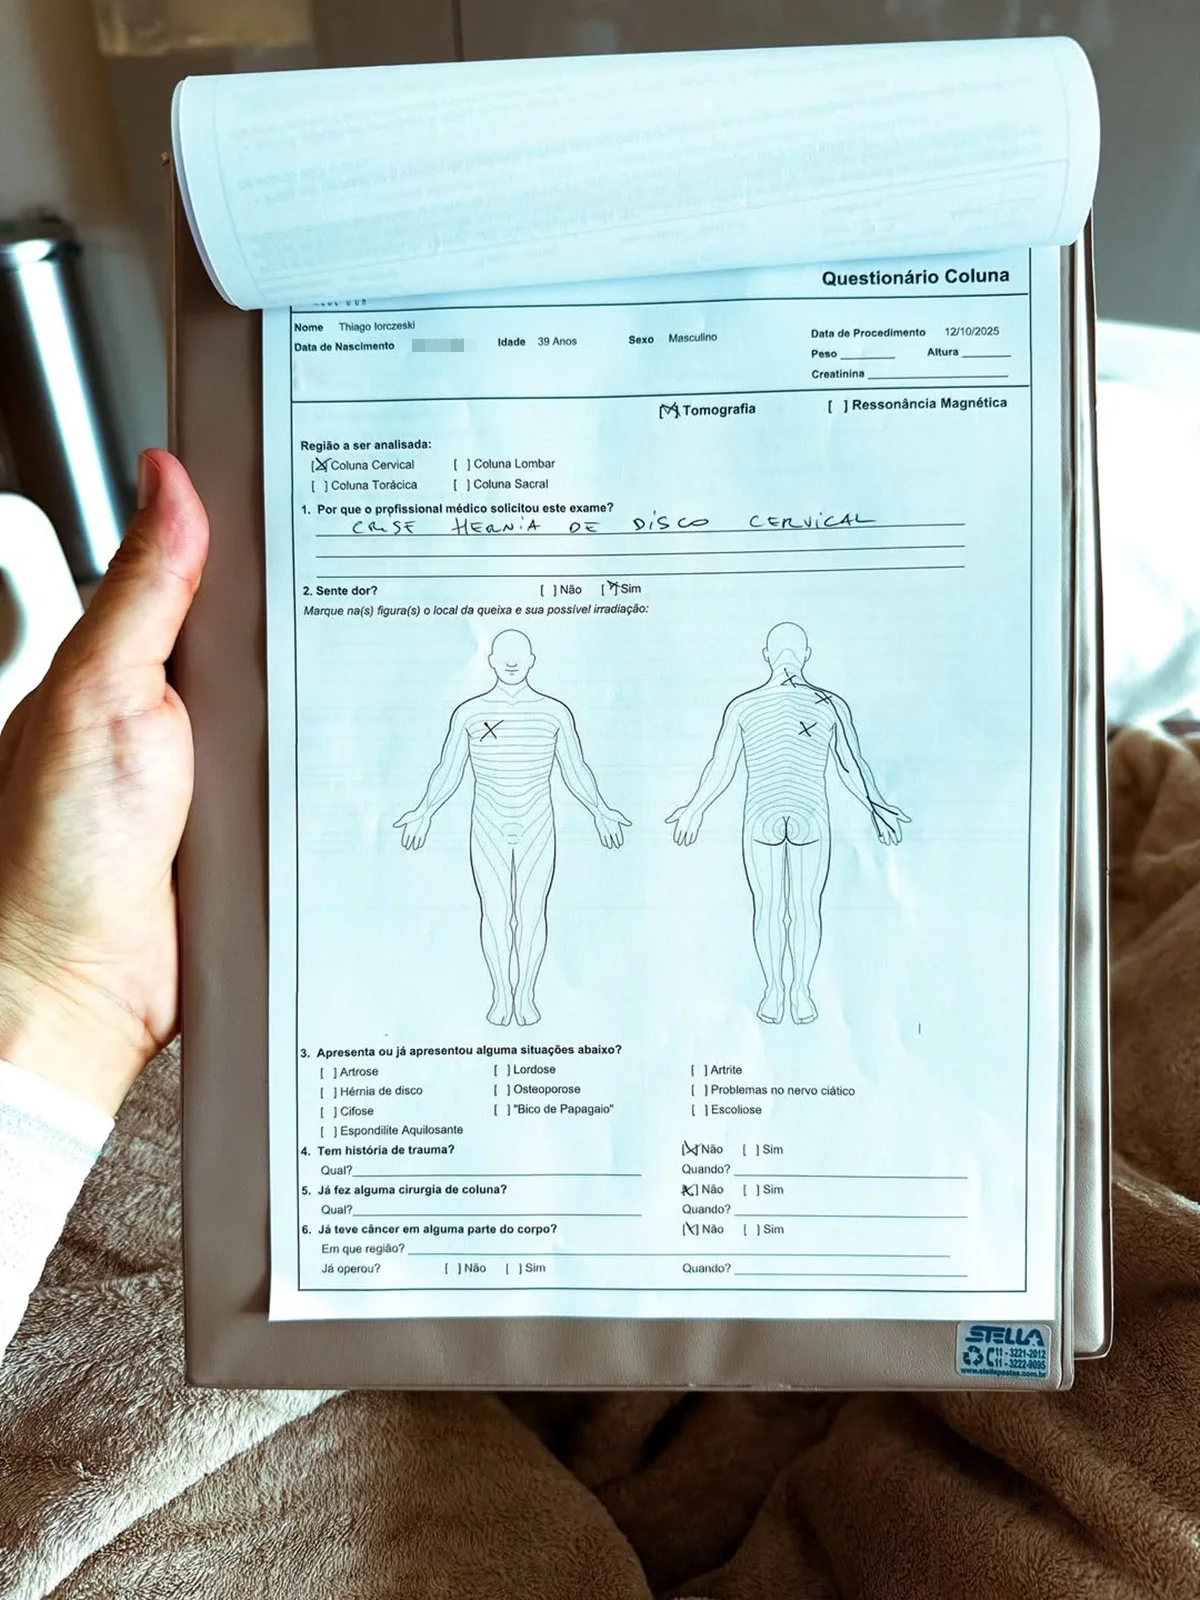

Tiago Iorc mostrou os exames que fez na unidade de saúde